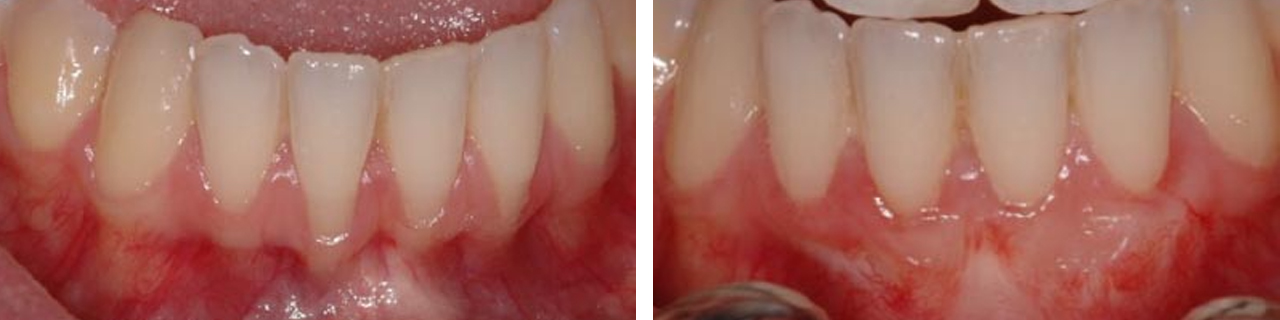

Cubrimiento

Cubrimiento de raíces expuestas.